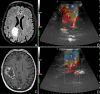

Introduction: Glioma surgery is aimed at obtaining maximal safe tumor resection while preserving or improving patient's neurological status. For this reason, there is growing interest for intra-operative imaging in neuro-oncological surgery. Intra-operative ultrasound (ioUS) provides the surgeon with real-time, anatomical and functional information. Despite this, in neurosurgery ioUS mainly relies only on gray-scale brightness mode (B-mode). Many other ultrasound imaging modalities, such as Fusion Imaging with pre-operative acquired magnetic resonance imaging (MRI), Doppler modes, Contrast Enhanced Ultrasound (CEUS), and elastosonography have been developed and have been extensively used in other organs. Although these modalities offer valuable real-time intra-operative information, so far their usage during neurosurgical procedures is still limited. Purpose: To present an US-based multimodal approach for image-guidance in glioma surgery, highlighting the different features of advanced US modalities: fusion imaging with pre-operative acquired MRI for Virtual Navigation, B-mode, Doppler (power-, color-, spectral-), CEUS, and elastosonography. Methods: We describe, in a step-by-step fashion, the applications of the most relevant advanced US modalities during different stages of surgery and their implications for surgical decision-making. Each US modality is illustrated from a technical standpoint and its application during glioma surgery is discussed. Results: B-mode offers dynamic morphological information, which can be further implemented with fusion imaging to improve image understanding and orientation. Doppler imaging permits to evaluate anatomy and function of the vascular tree. CEUS allows to perform a real-time angiosonography, providing valuable information in regards of parenchyma and tumor vascularization and perfusion. This facilitates tumor detection and surgical strategy, also allowing to characterize tumor grade and to identify residual tumor. Elastosonography is a promising tool able to better define tumor margins, parenchymal infiltration, tumor consistency and permitting differentiation of high grade and low grade lesions. Conclusions: Multimodal ioUS represents a valuable tool for glioma surgery being highly informative, rapid, repeatable, and real-time. It is able to differentiate low grade from high grade tumors and to provide the surgeon with relevant information for surgical decision-making. ioUS could be integrated with other intra-operative imaging and functional approaches in a synergistic manner to offer the best image guidance for each patient.